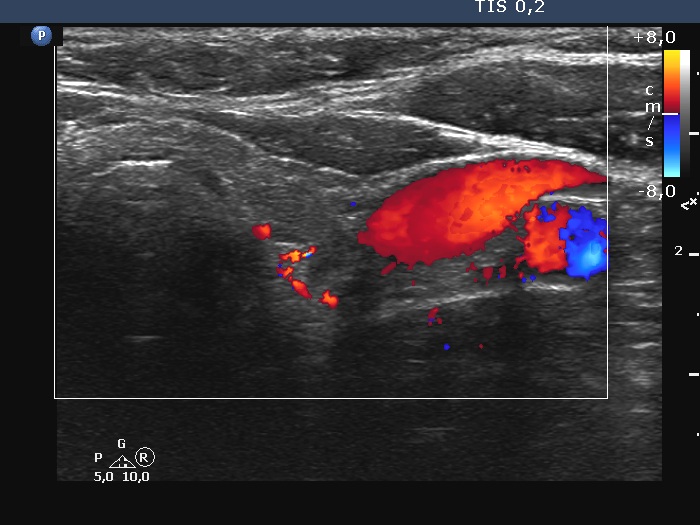

Right lobe, longitudinal scan

Left lobe, transverse scan, color Doppler mode. The vascularity is scanty.